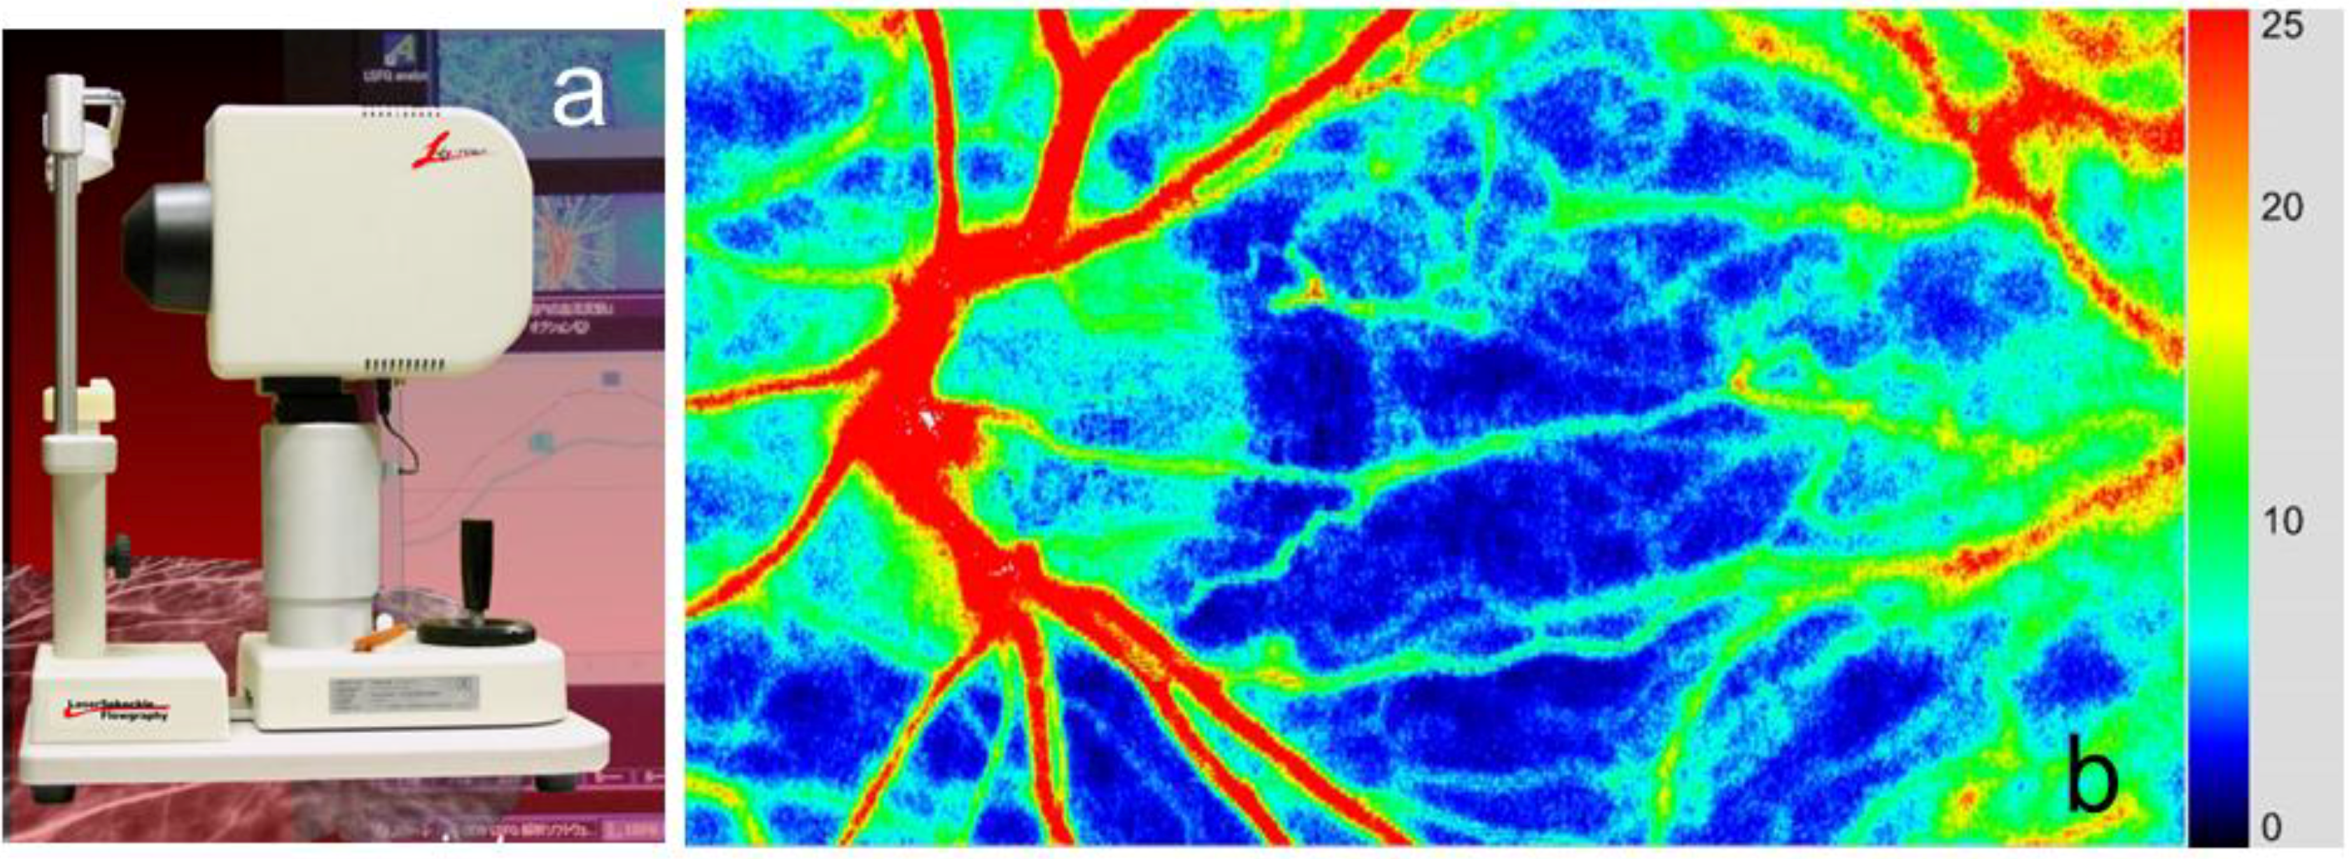

The new parameter MBR is approximately proportional to SBR. The new LSFG system has demonstrated a better spatial resolution of the blood flow map of the human fundus than the original system so that some thin vessels as well as the choroidal network have become visible. The observation area has been expanded to 6 × 3.8 mm square, which is 24 times larger than the original LSFG system. Despite the different scanning intervals, the time resolution is nearly the same as the original system with 30 maps/s. Consequently, the CCD camera can successfully replace the special area sensor used in the original system. The block diagram and appearance of the updated model of LSFG, LSFG-NAVI, and an example of the color map obtained by this device are shown in Figure 2 and Figure 3. Additionally, the LSFG-NAVI-OPE model was developed recently for ocular blood flow measurement in subjects in a supine position [8]. Schema and the photograph of this device are shown in Figure 4.

Figure 3.

Appearance of the LSFG-NAVI device (a) and an example of its color map (b).